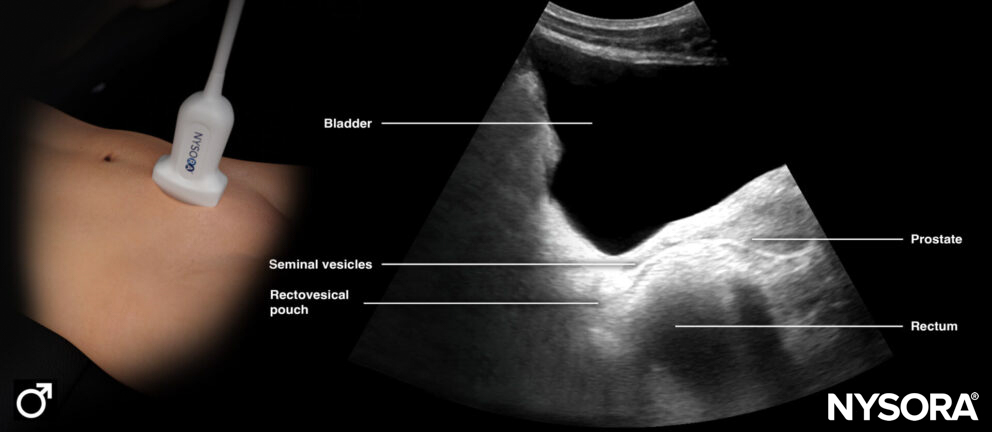

Longitudinal ultrasound view of the bladder (male).

Longitudinal Reverse Ultrasound Anatomy of the bladder (male).